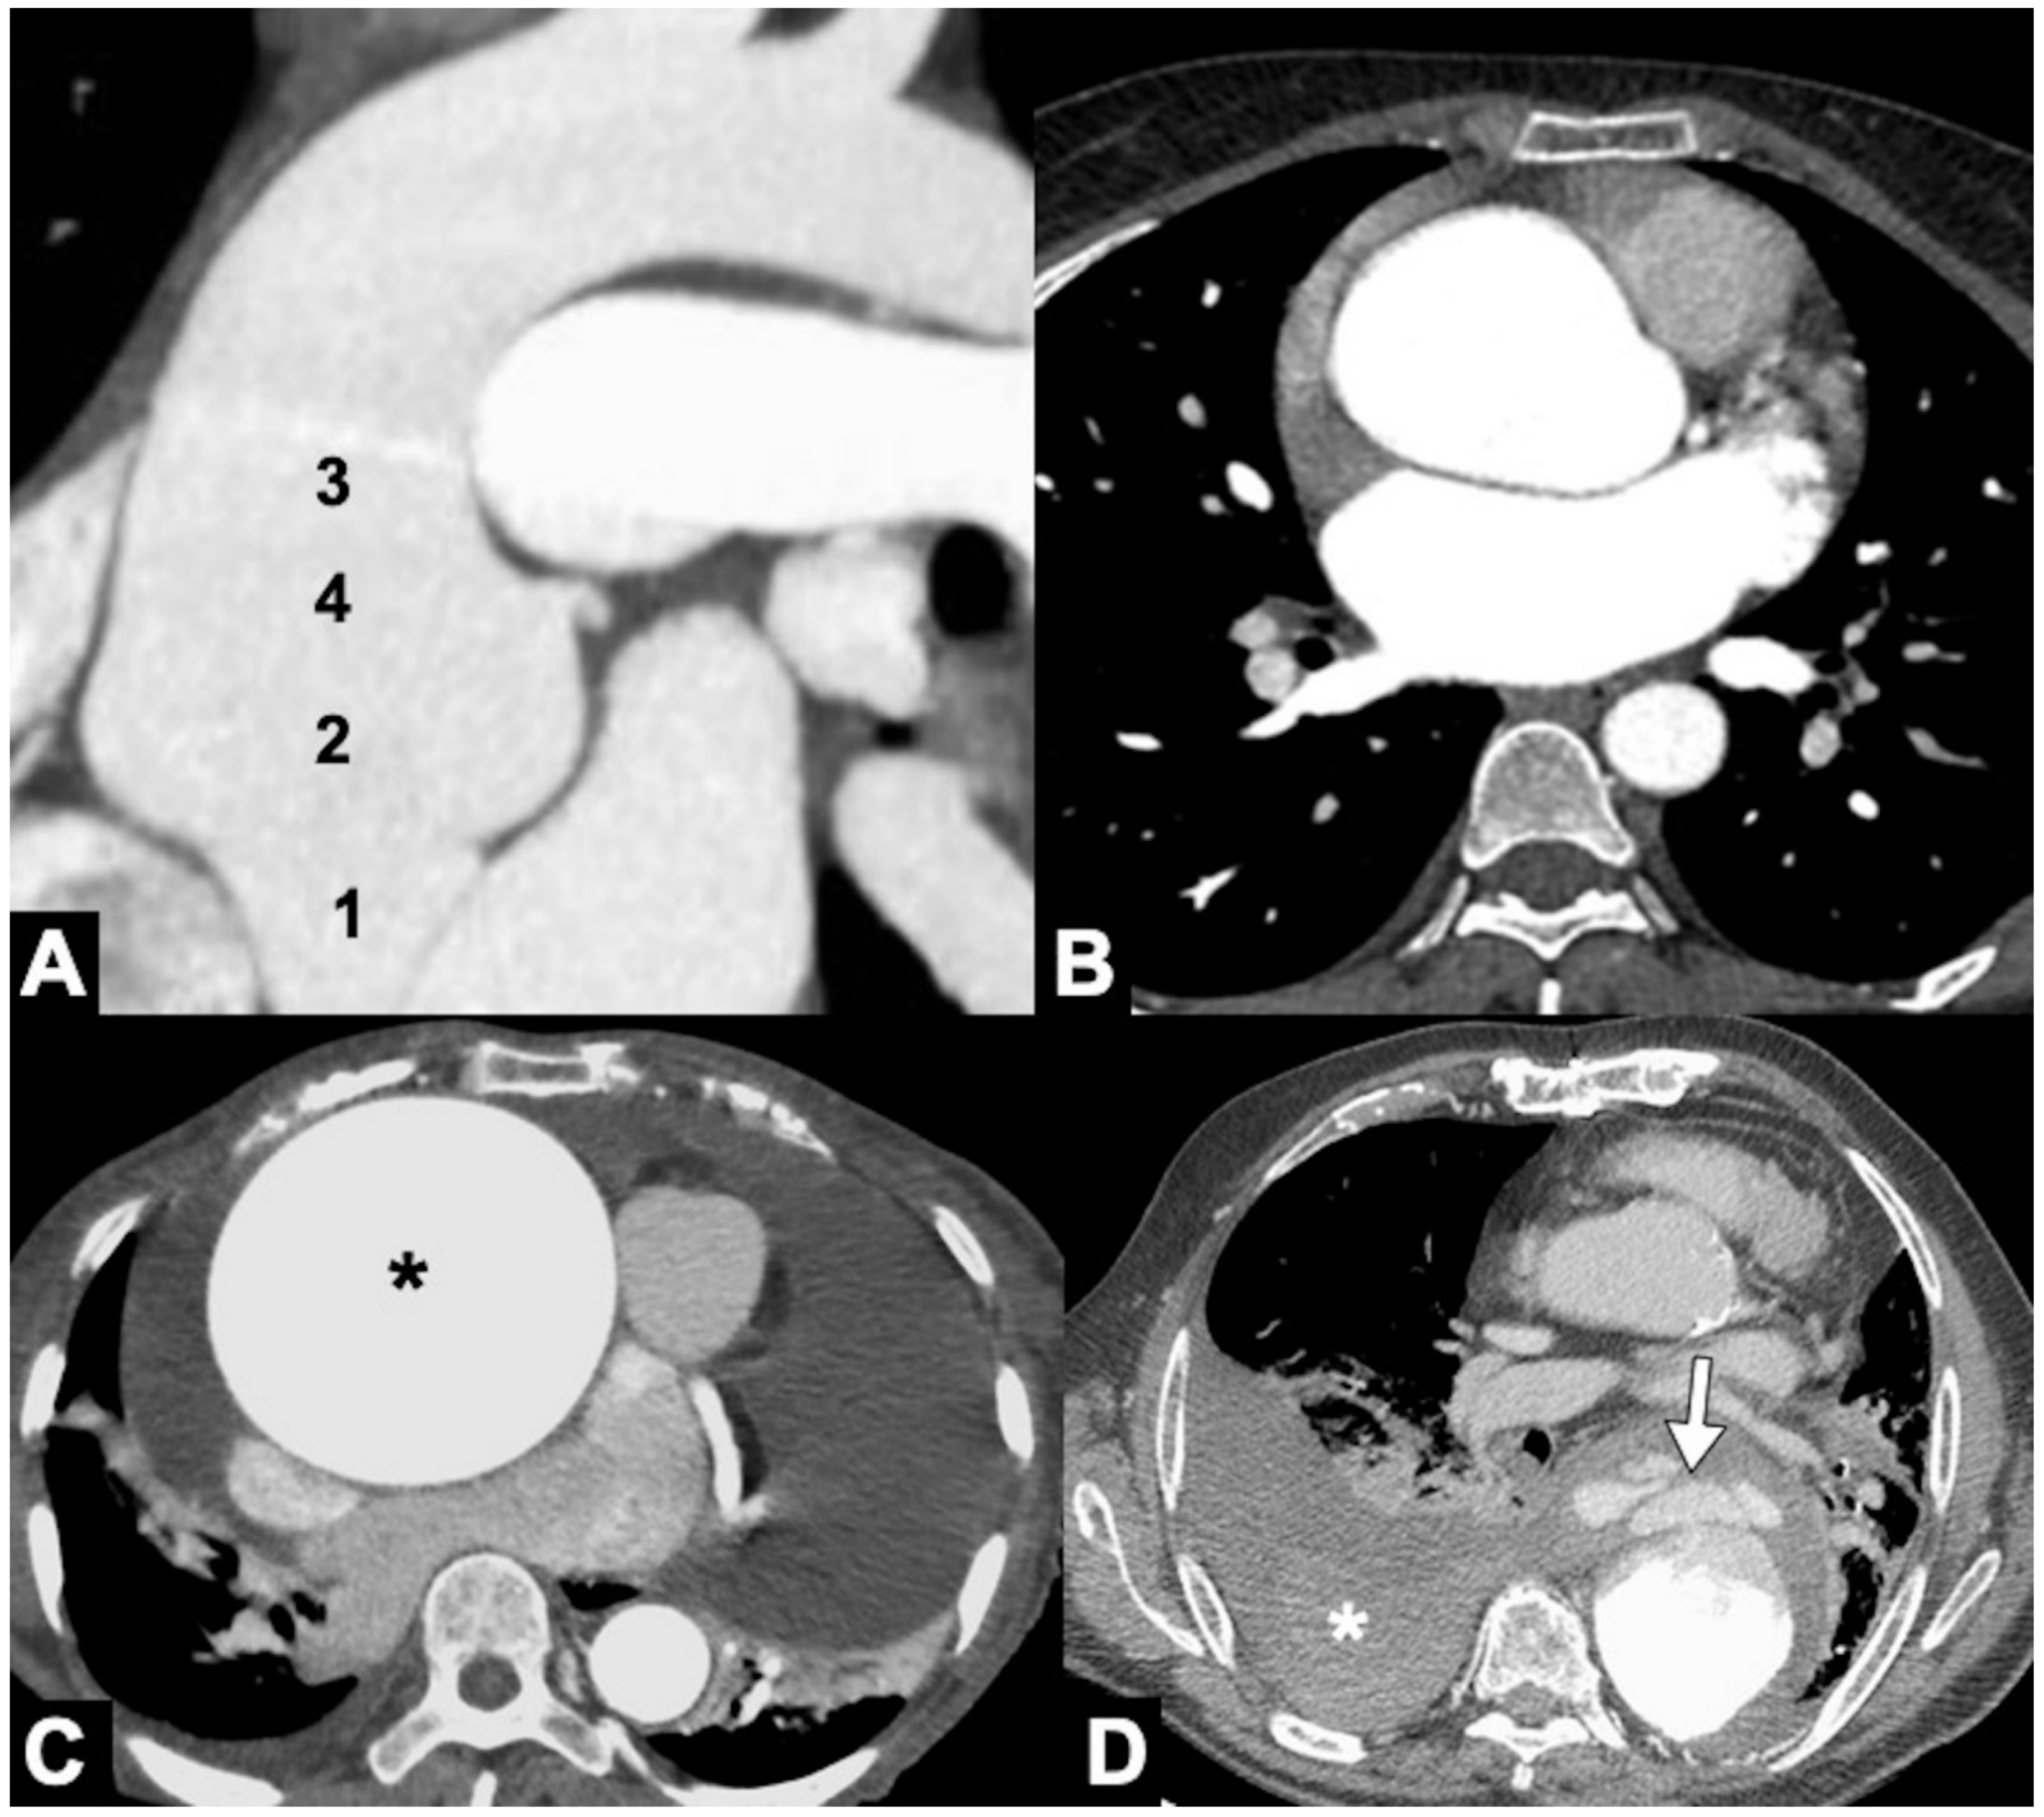

Because an abdominal aortic aneurysm occurs in 28% of patients with a TAA, it is important that the initial evaluation includes the entire thoracoabdominal aorta. TAAs are classified by location as affecting more commonly the ascending aorta (36%), aortic arch (34%), or DTA (30%) [103]. Annuloaortic ectasia is a condition with dilated sinuses of Valsalva along with effacement of the sinotubular junction (STJ) producing a pear-shaped ascending aorta commonly seen associated with Marfan syndrome and other connective tissue disorders (Figure 11A,B). The Crawford classification modified by Safi describes five types of thoraco-abdominal aortic aneurysms [104]. In the evaluation of TAA, CTA accurate depiction of aortic caliber on centerline imaging, morphology, relationship to the aortic arch vessels and the presence of thrombus or ulceration are of importance in deciding whether and how to intervene [104,105]. Accurately measured maximal aortic diameter is currently the primary metric used to guide surveillance strategy and the timing of surgical/endovascular intervention for patients with TAA (Figure 11C). The generally accepted aneurysm growth rate is 4 mm/year, and intercurrent dissection is associated with a more rapid growth rate. When the size of the aorta reaches its biomechanical “hinge point,” usually about 5.5 cm in diameter for ascending aorta and 7 cm for DTA, wall integrity rapidly declines, growth accelerates, and the incidence of complications rapidly increases. A rupture occurs when mechanical stresses on the wall exceed the wall strength, and as dictated by the law of Laplace, the rupture risk increases with aneurysmal size (Figure 11D) [106,107]. Clinical subtle and non-specific symptoms may already correspond to clear radiological signs of impending rupture. As far as the most accepted widespread criteria are represented by the maximum diameter and the expansion rate, there are other important imaging features that radiologists must be aware of, to promptly detect potentially life-threatening conditions (Table 6). These features are considered by most authors as signs of impending rupture (SIR) and include, amongst others, (1) a hyper-attenuating crescent sign, (2) focal wall discontinuity of circumferential calcifications (Figure 12A), (3) aortic bulges or blebs, and (4) a draped aorta sign or periaortic stranding [108,109]. These signs are mostly based on CT characteristics of the mural thrombus. Aneurysms are indeed often characterized by a thrombus lining the walls and by a patent lumen. As some authors consider the width of the mural thrombus a protective factor for aneurysm stability, the reduction in its width is considered a criterion of higher rupture risk [110]. Amongst the aforementioned SIR, the “hyperattenuating crescent sign” results from intraluminal blood creating a fissure that transits through the unstable mural thrombus to the intimal margin, forming a typical semilunar shape [111].

Figure 11. CTA of thoracic aorta aneurysms. (A) Marfan syndrome, a multisystem connective tissue disease caused by a defect in the protein fibrillin 1, and annuloaortic ectasia in a 42-year-old man. Sagittal MIP reconstruction image shows a proximal dilatation of the aortic anulus (1), sinuses of Valsalva (2) along with effacement of the STJ (4) producing a pear-shaped ascending aorta (3). (B) Axial CTA image shows sinuses ectasia in the same patient. In Marfan syndrome, a cut-off value of 5 cm of the ascending aorta diameter is recommended for surgical repair. (C) Axial CTA image shows a 12 cm ascending aorta aneurysm (asterisk) and a large mediastinal effusion. The risk of rupture of TAAs increases with size of the aneurysm according to Laplace’s law. (D) Axial CTA image shows a ruptured atherosclerotic aneurysm of the descending thoracic aorta. Note the high-attenuation fluid in the right pleural space, representing acute hemothorax (asterisk), and contrast medium extravasation from the aortic lumen (arrow).